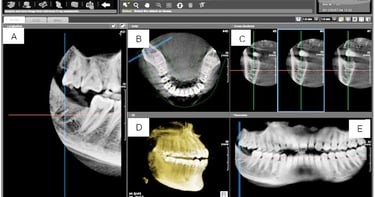

CBCT (rontgen 3 dimensi)

CBCT (Cone Beam Computed Tomography) adalah teknologi rontgen gigi 3 dimensi yang menghasilkan gambaran detail struktur gigi, tulang rahang, saraf, dan jaringan sekitar secara menyeluruh.

Berbeda dengan rontgen biasa yang hanya menampilkan gambar 2D, CBCT memberikan visualisasi tiga dimensi yang lebih akurat untuk membantu dokter dalam menentukan diagnosis dan perencanaan perawatan.

Keunggulan :

✔ Gambar 3 Dimensi yang Detail & Presisi

✔ Diagnosis Lebih Akurat

✔ Perencanaan Implant & Bedah Lebih Aman

✔ Ideal untuk Kasus Kompleks

✔ Radiasi Lebih Terkontrol